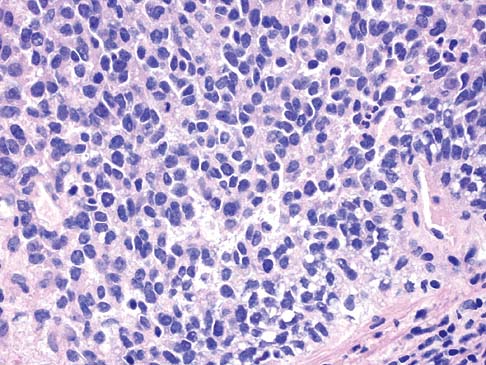

Ewing's sarcoma refers to a rare and aggressive form of bone cancer. The Ewing's sarcoma market has seen significant growth in its trajectory, propelled by various influential factors. The primary catalyst for the market's expansion is the increasing incidence of Ewing's sarcoma. The rise in prevalence of this rare cancer necessitates diagnosis and treatment options. Advanced diagnostic tools and techniques play a crucial role in the market's growth by enabling earlier and more accurate detection of Ewing's sarcoma. Imaging technologies like MRI and PET scans contribute to better visualization and staging of the disease. The therapeutic landscape for Ewing's sarcoma has expanded significantly, with pharmaceutical companies and research institutions investing heavily in R&D activities. This includes the development of novel treatment modalities, such as targeted therapies and immunotherapies.